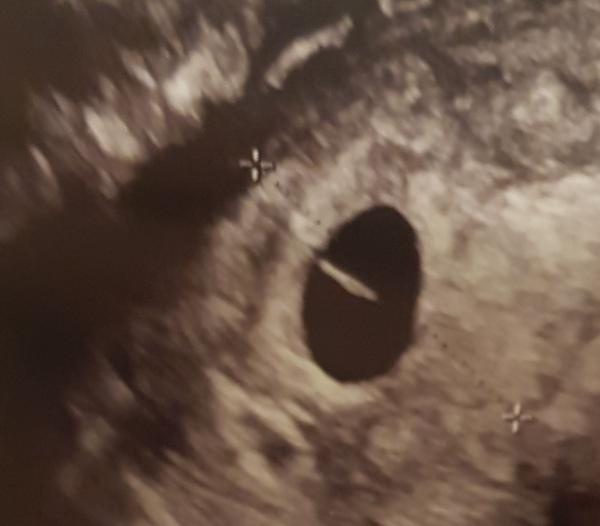

Hej, kanske lite fel forum, är beräknad i aug 2020 men var på ett tidigt vul 6+2 någon som kan hjälpa mig tyda bilden?

Då var hon tvungen att göra ett ultraljud så jag fick se bebisen i magen. Hjärtslagen och hur den rörde på sig.